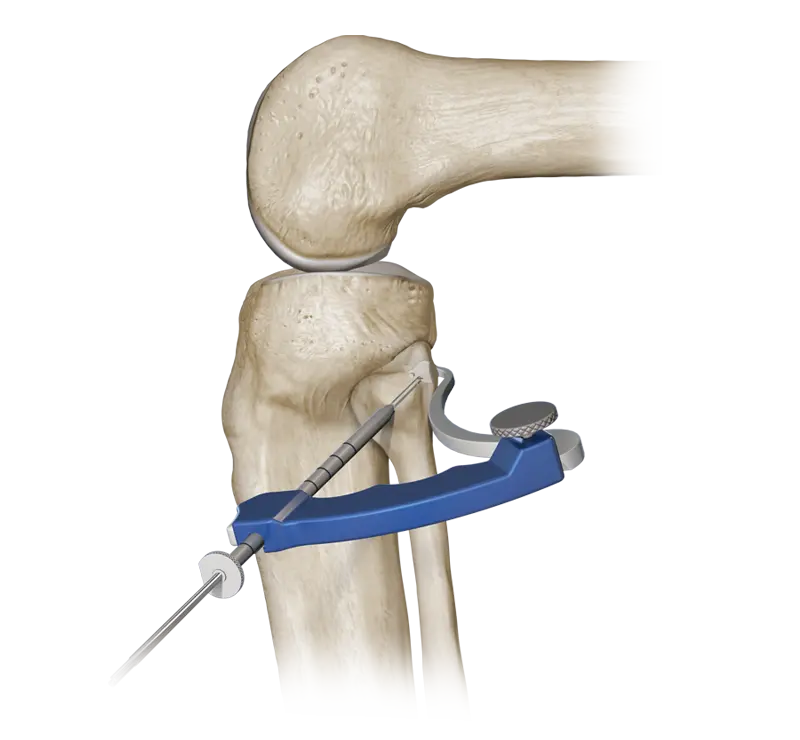

Ligament reconstruction is commonly recommended for injuries such as ACL tears, PCL injuries, MCL damage, LCL tears, and multi-ligament instability. These issues often occur due to sports injuries, sudden twists, accidents, or repetitive strain. The procedure involves replacing the torn ligament with a graft to restore natural stability and strength to the joint.

With minimally invasive arthroscopic techniques, advanced graft options, and rapid recovery protocols, HappyKnees helps patients return to their active lifestyle safely and confidently.

HappyKnees is a trusted center for sports injury and ligament reconstruction surgeries in Mumbai. Dr. Akash Saraogi specializes in arthroscopic ligament reconstruction using:

✔ High-precision graft placement

✔ Modern fixation techniques